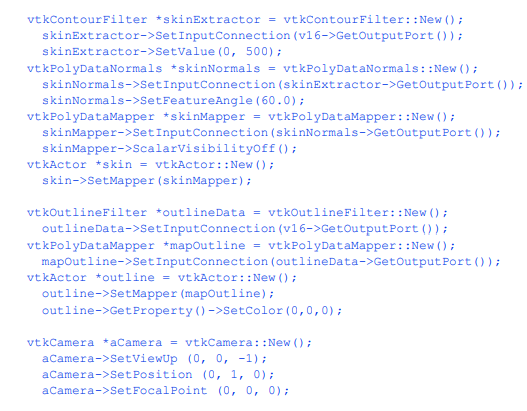

我们选择使用的过滤器是vtkMarchingCubes。我们还可以使用vtkContourFilter,因为它将自动创建一个vtkMarchingCubes实例,因为它将委托给特定数据集类型的最快的子类。类vtkPolyDataNormals用于为数据生成漂亮的表面法线。vtkMarchingCubes也可以生成法线,但有时法线直接来自曲面(vtkpolydatanorals)而不是来自数据(vtkMarchingCubes)会获得更好的结果。为了完成这个示例,我们从等值面生成器vtkMarchingCubes获取输出,并通过vtkPolyDataMapper和vtkActor将其连接到映射器和actor。下面是c++代码。

为了提供等值面的上下文,在数据周围创建一个轮廓。初始视图设置在像素大小的窗口中。由于移动相机命令移动到数据,剪辑平面重置,以确保等值面是完全可见的。图12 - 2显示了患者的皮肤图像。

我们可以通过多种方式改进这种可视化。首先,我们可以为皮肤选择更合适的颜色(和其他表面属性)。我们使用vtkProperty方法SetDiffuseColor()将皮肤颜色设置为肉色。我们还在皮肤表面添加了一个镜面组件。接下来,我们可以添加与各种解剖特征相对应的额外等值面。这里我们选择通过添加额外的管道段来提取骨表面。它由筛选器vtkMarchingCubes、vtkPolyDataMapper和vtkActor组成,就像我们对皮肤所做的一样。最后,为了提高系统的渲染性能,我们从输出中创建三角形条

轮廓的过程。这需要添加vtkStripper。图12 - 3显示了生成的图像,下面是该管道的c++代码。